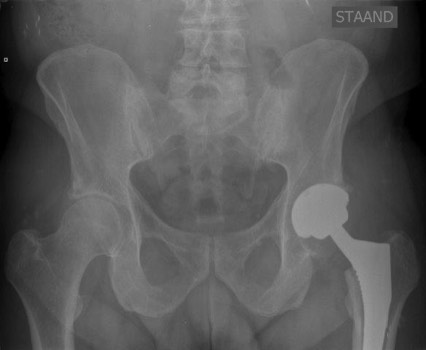

• Heupprothese: Bij ernstige artrose kan een heupprothese geplaatst worden om het beschadigde gewricht te vervangen.

Een heupprothese is een chirurgische ingreep waarbij het beschadigde heupgewricht vervangen wordt door een kunstmatige prothese. Deze prothese bestaat uit materialen zoals metaal en kunststof en heeft als doel om de functionaliteit en mobiliteit van de heup te herstellen. Na een heupprothese operatie volgt een herstelproces dat geleidelijk verloopt. In de eerste dagen na de ingreep is rust en fysiotherapie belangrijk om de spieren te versterken en het gewricht soepel te houden. Geleidelijk aan worden activiteiten zoals lopen, staan en traplopen weer opgebouwd onder begeleiding van medisch personeel. Het volledige herstel kan enkele maanden in beslag nemen, waarbij geduld, discipline en opvolging van het revalidatieprogramma cruciaal zijn voor een succesvolle revalidatie na een heupprothese operatie.